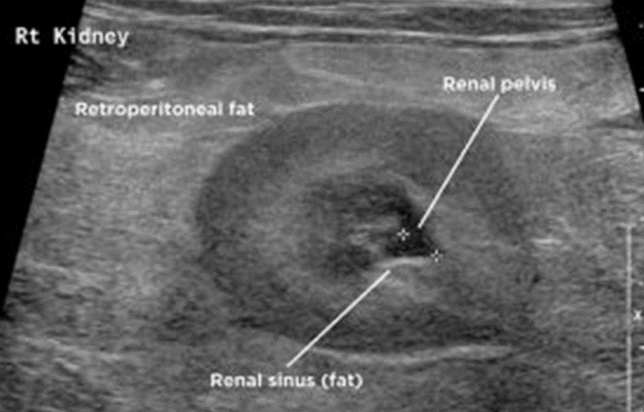

what abnormalities may be seen on ultrasound in patients with pyelonephritis?

U/S findings are nonspecific:

-renal pelvic dilation (+/- echogenic fluid - suggestive of pus)

-dilated ureter

-blunting of renal papilla

-hyperechoic retroperitoneal fat around kidney